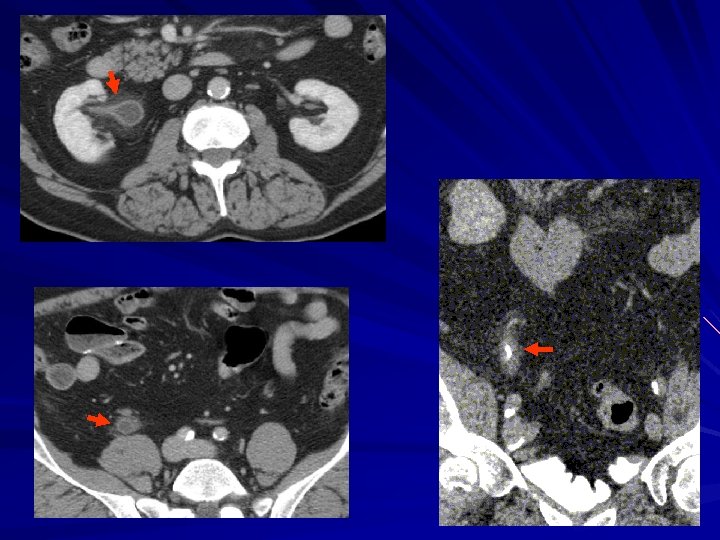

CTU and “regular” CT 66 Y. O. man 1 year post partial nephrectomy for POST. RCC. VIEW New hydronephrosis on CT, suspect rec. obstructing tumor.